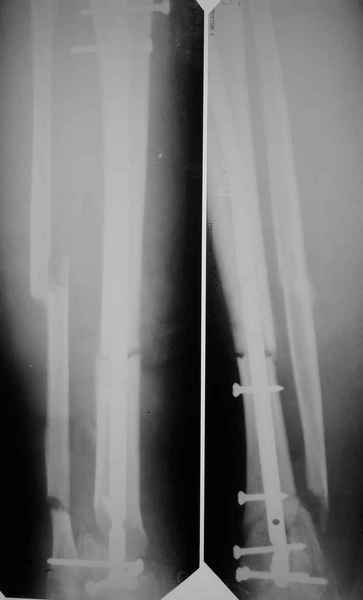

[Ortho] Метатарзал краш синдром в порочном сращении (эквинусная стопа), несращение сегментарного перелома костей голени после БИОС , ПТФБ, ХВН СЕАР С-6.

уважаемые коллеги помогите как с этим разобраться